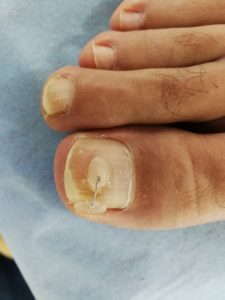

L’orthonyxie est une technique podologique qui permet de corriger les courbures d’ongles excessives grâce à une agrafe active ou passive. Elle est réalisée lorsque l’ongle génère des conflits entre la plaque unguéale (ongle) et les tissus péri-unguéaux (le sillon ou le bourrelet). L’orteil devient alors douloureux, voir extrêmement douloureux.

• lorsque l’ongle présente une déformation (ongle en « tuile de provence », ongle en volute, plicature unilatérale ou bilatérale);

• lorsque l’ongle est incarné de manière chronique ou lors de la présence de cors périunguéaux. Plusieurs causes peuvent entraîner l’apparition d’un ongle incarné : le plus souvent lié à une mauvaise coupe d’ongle, plicature d’ongle, ongles cassants, traumatismes répétés (liés au sport par exemple)…

L’orthonyxie est un appareillage inspiré de l’orthondontie. Il est constitué d’encrages en résine photopolymérisable et d’un fil à mémoire

de forme. En effet, l’orthonyxie consiste à fixer sur l’ongle un fil titane positionné entre deux ou trois plots lui permettant de créer une

tension constante et contraire à la déformation de l’ongle. L’ongle s’aplanit alors au fur et à mesure de la repousse.

En fonction de la qualité et de l’importance de la déformation de l’ongle, plusieurs techniques sont envisageables : contention passive (languette de décompression) ou contention active (fil titane à traction unilatérale ou bilatérale).